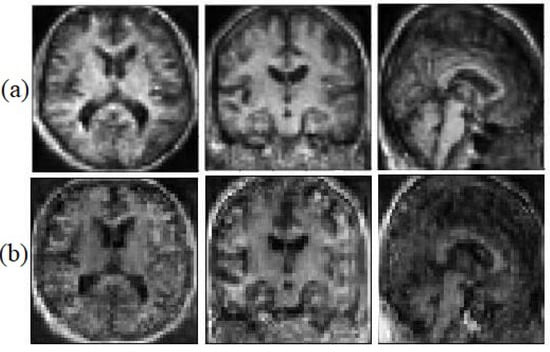

We believe that the geometrical and edges information can help the model to face the saturation problem less. This information helps the generator to be able to catch up with the discriminator faster. Figure 6, illustrates the synthetic images with geometrical information and without geometrical information.

Figure 6.

Synthetic MRI with the Sobel filter (a) and without the Sobel filter (b).

5.2. Structural Analysis

Visual analysis is one of the most common ways to evaluate generated images. To ensure that the structural information is not missed, the generated images have been evaluated after segmenting the generated image as well. We segmented each image into three classes (white matter, grey matter, and CSF) to examine if the model has generated miss-placed voxels. Figure 7, illustrates the ground truth segmented T1 weighted MRI and the synthetic image after the segmentation.

Figure 7.

The ground truth (a) and the synthetic T1 weighted MRI (b).

The proposed model almost predicts the structure of the grey matter correctly so the generated grey matter can be used in order to correct the partial volume effect, on PET images. We have replicated the analysis with 10 subjects and measured the average voxel values between the ground truth and the generated images for each tissue. Figure 8, represents the average of voxel values.